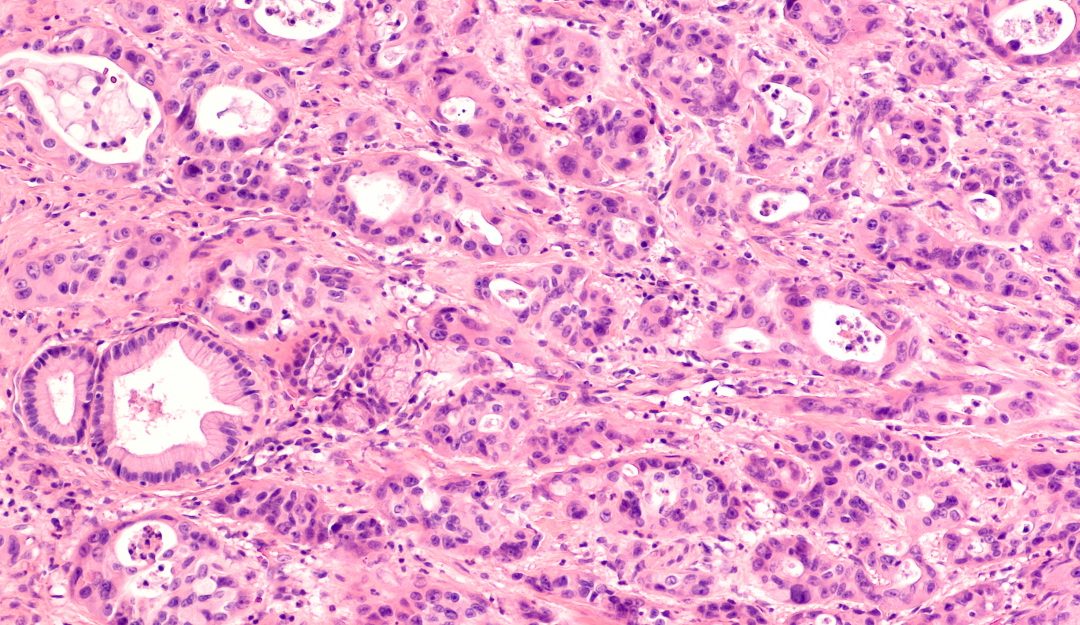

Detecting pancreatic disease using artificial intelligence and human ingenuity Published: The pancreas is a vital organ for digestion and metabolism, so when issues arise, it is important to diagnose and treat the issue effectively. However, pancreatic diseases are...